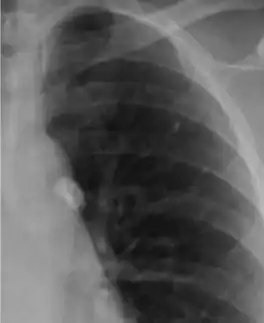

![]() Рентген грудной клетки со следами очага Гона |

Очаг Гона (англ. Ghon's focus, Ghon focus) — очаг первичного поражения лёгких при туберкулёзе, обычно в рамках первичного туберкулёзного комплекса (то есть в сочетании с регионарной лимфаденопатией). Первоначально представляет собой небольшой (размером от булавочной головки до плода вишни) очаг гранулёматозного воспаления, который можно обнаружить на рентгенограмме грудной клетки[1]. В большинстве случаев зарубцовывается, оставляя после себя капсулу из соединительной ткани, в которой впоследствии откладываются соли кальция, но в некоторых случаях может развиться в полноценный туберкулёз, особенно если у пациента ослабленный иммунитет[1].